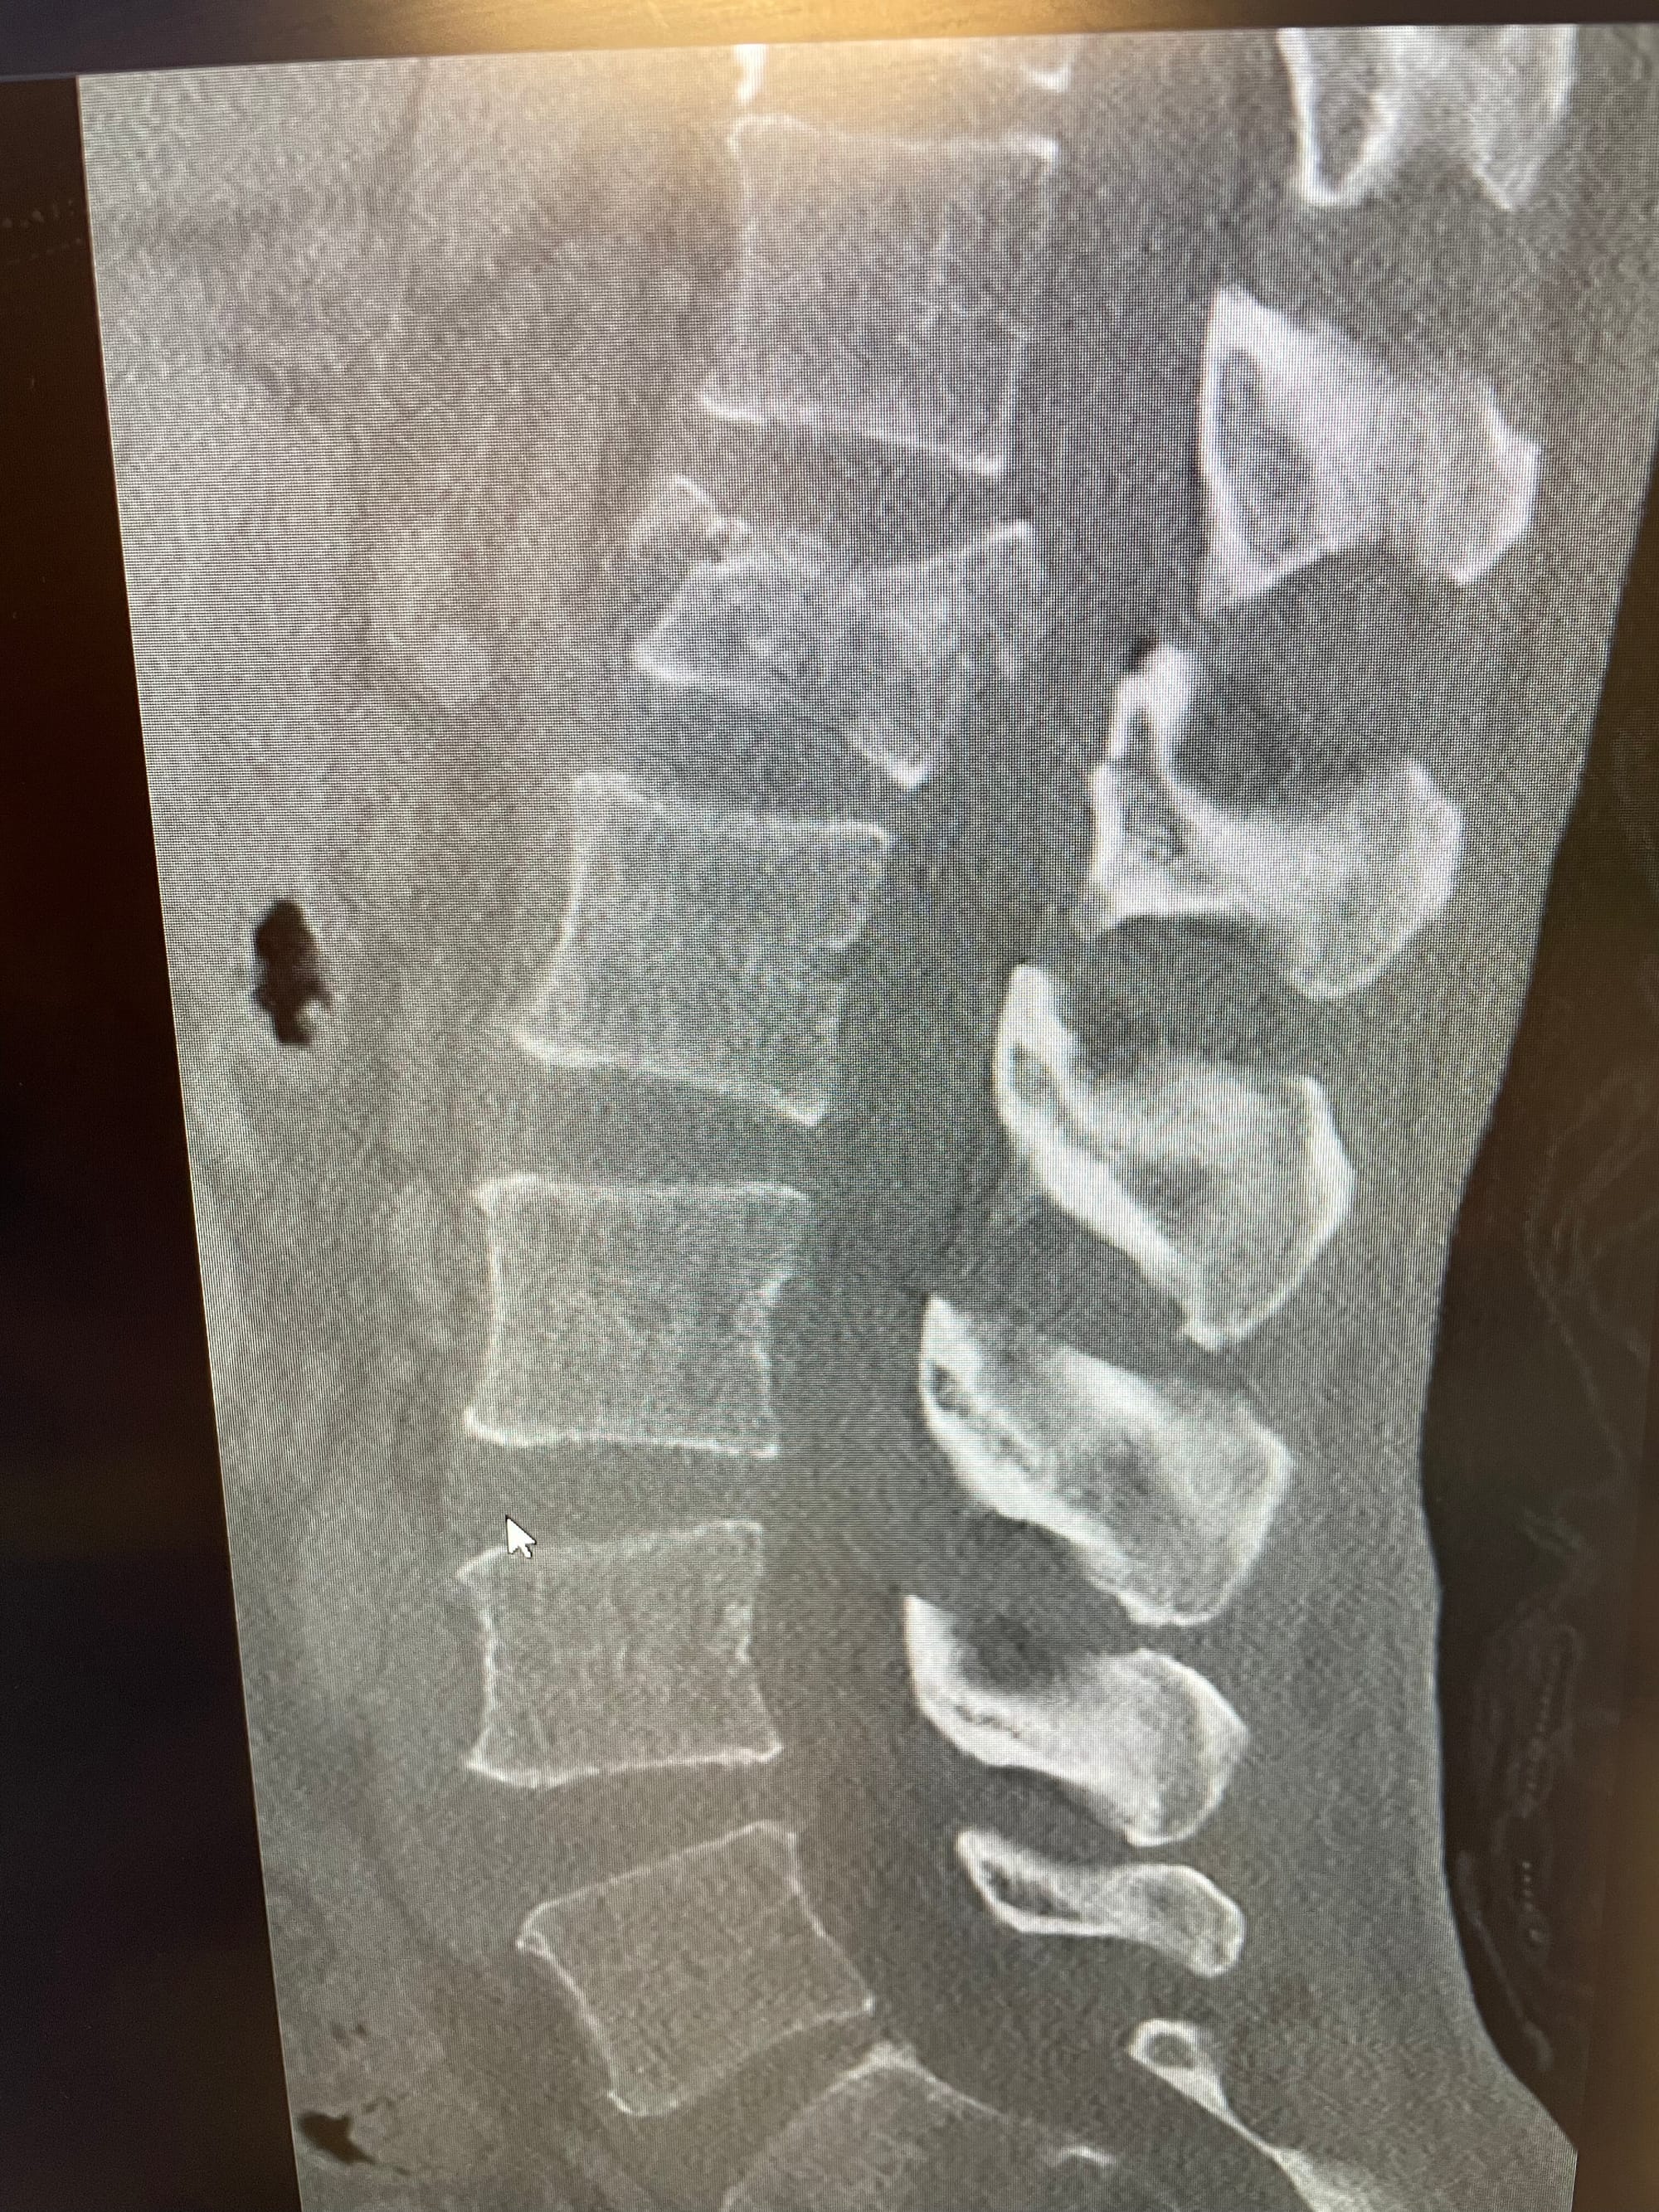

I had my first follow-up meeting with the surgeon who worked on my back. Before the meeting, they took X-rays, and she was happy with how things looked. I asked about current physical restrictions, and I'm allowed to do anything I want using my best judgement. I also asked questions about the surgery, and Cathy and I got to view old and new X-rays and CAT scans. They also took an MRI, but I don't think we saw it a the meeting. Actual X-rays of my spine before surgery and this week (with hardware) are shown below.